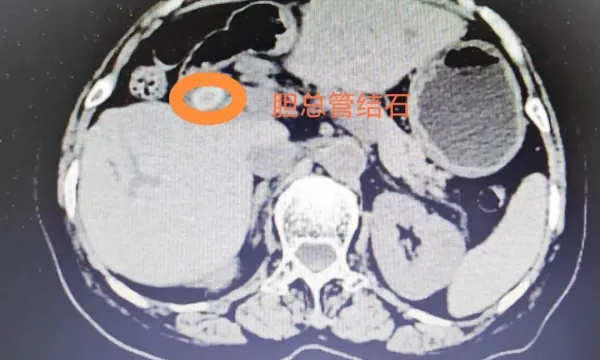

患者李某因“反复上腹部疼痛不适”入院,检查发现肝内外胆管多发结石。因曾有过多次行ERCP(经内镜逆行胰胆管造影取石)治疗和腹腔镜胆总管切开取石、腹腔镜肝部分切除手术史,再次行腹腔镜手术难度大,且仅能处理胆总管结石,无法解决肝内胆管结石的问题。

肝胆外科主任邱伟与团队成员经过充分术前讨论,决定为李某实施经皮经肝胆道镜取石术(PTCS)。术中,在超声的精准引导下,医生建立微创通道,利用胆道镜和碎石设备,将肝内外胆管结石逐一击碎并取出。手术过程顺利,术中出血极少,患者术后第一天便能下床活动,很快康复出院。

此次手术的成功,是汉滨区第一医院肝胆外科开展经皮经肝胆道镜取石术(PTCS)的一次生动实践,也标志着汉滨区第一医院在复杂胆道结石治疗领域正式迈入“超微创”新阶段。该技术仅需在皮肤建立约0.5厘米的微小通道,即可直达肝内胆管,在直视下碎石取石,具有显著优势:创伤小、出血少,术中平均出血量仅20毫升;恢复快、住院周期短,术后平均住院约6天;取石高效彻底,结石清除率达93%以上;尤其适合腹腔粘连严重、高龄及心肺功能较差、无法耐受传统开腹手术的复杂患者。